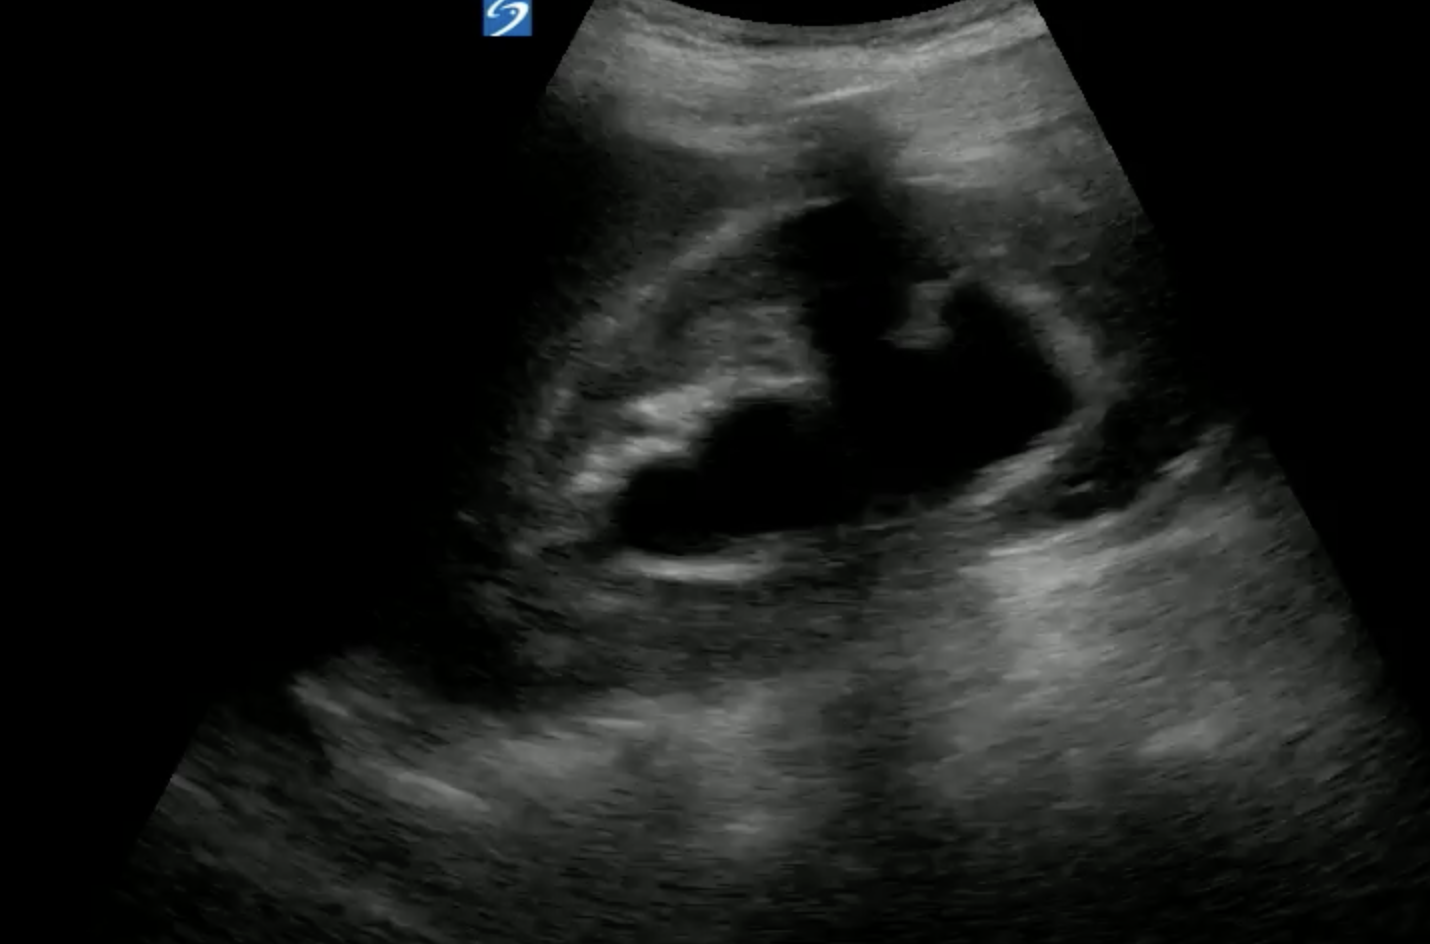

EDUS revealed this bilaterally:

Interestingly, I couldn't see a dilated ureter at the pelvis. Also there was no ureteric dilatation at the VUJ and her ureteric jets were normal. Her bladder post void volume was small excluding an outlet obstruction. Aorta and retroperitoneum was NAD.

If you look closely at her US images, you can see that her cortex is normal thickness bilateral despite quite significant "hydronephrosis". Also on the left, the anechoic areas seem discrete and round.